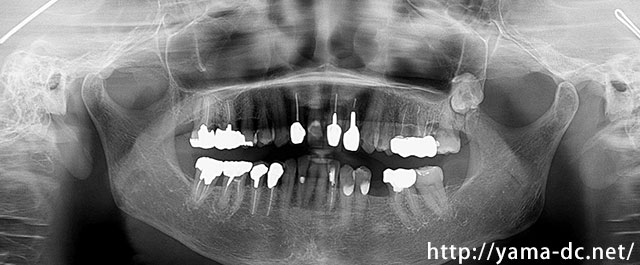

CTを用いることで従来の平面的なレントゲン画像では難しいとされる顎の骨を立体的に確認することができます。

きちんと神経の位置や骨の状態を確認した上で治療計画を立て、患者様に安心・安全なインプラント治療をご提供しています。

もっとも多い奥歯の1本欠損によるインプラント治療を説明します。